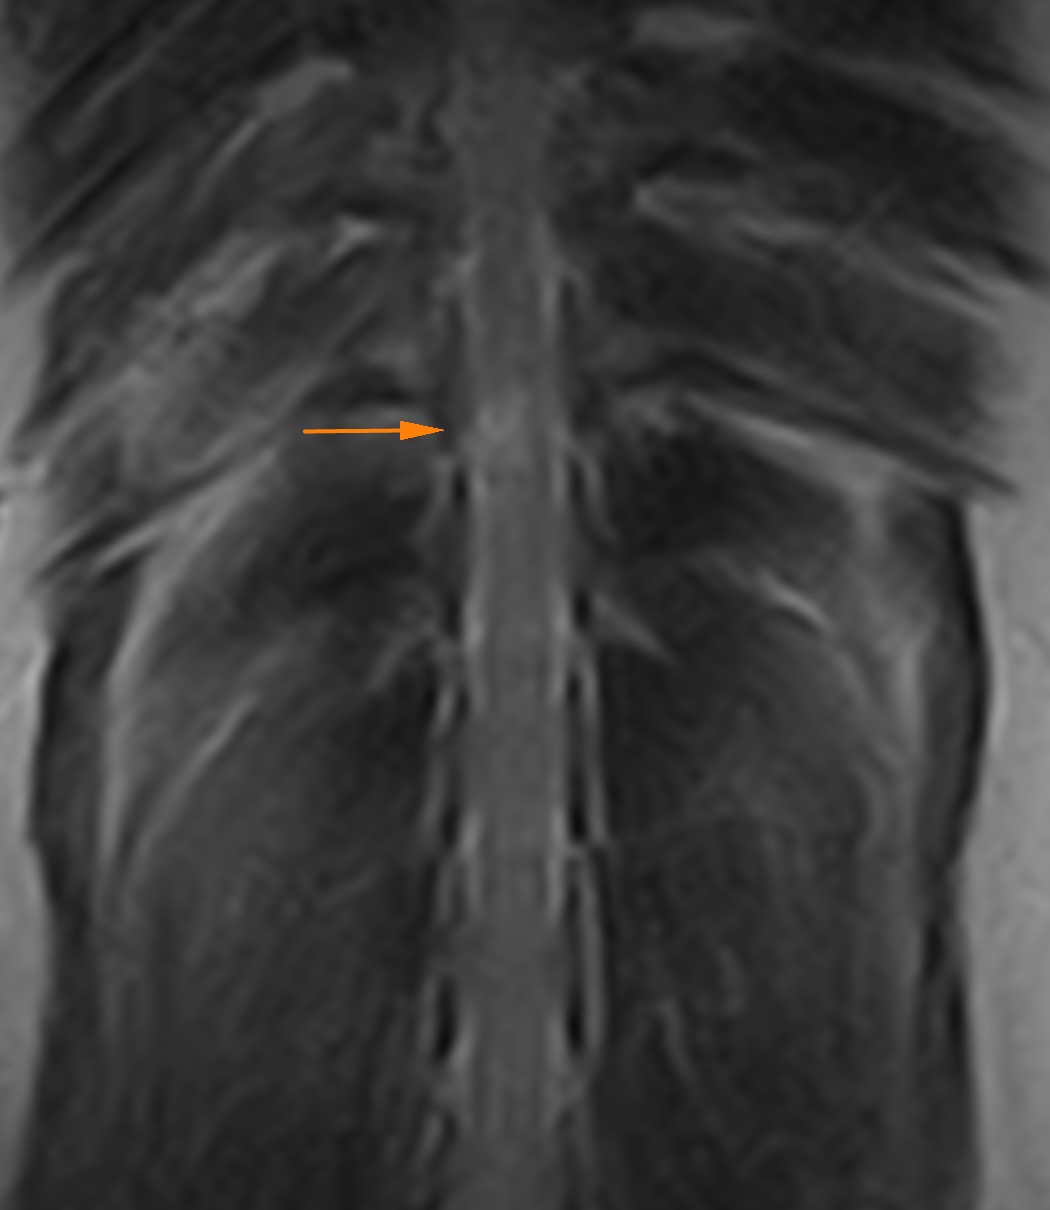

脊髄梗塞

中年齢の小型犬が、遊んでいる最中に急に後ろ足が動かなくなったとのことで精査の依頼がありました。

起立することができず、排尿の感覚も低下している状態でした。

MRI撮影を行うと脊髄の一部に異常があり、脊髄梗塞と診断しました。

これは線維軟骨といわれる微小な物質が、脊髄の血管に閉塞することで神経機能が麻痺してしまう病気です(脳梗塞と似ています)

特効薬はなく、理学療法を行うことで徐々に改善が期待できます。